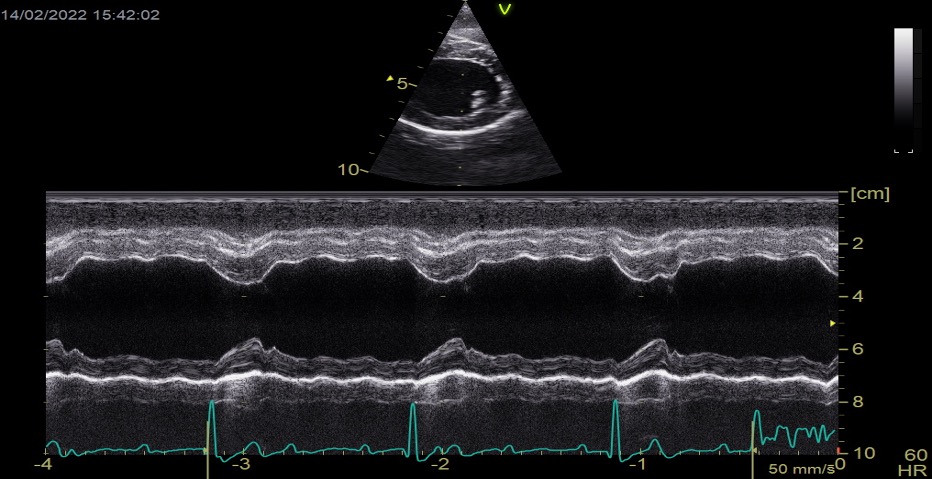

Pregunta 2

En un paciente con enfermedad valvular degenerativa mitral, en estadio C con diagnóstico previo de edema pulmonar, tras el tratamiento con furosemida, su perfil de flujo transmitral previo mostraba una pseudonormalización, con una velocidad pico E de 1,1 m/s. En la revisión, este es ahora su perfil de flujo transmitral. ¿Qué está pasando? ¿Qué más podemos hacer por el paciente?

Existe una progresión de la patología hacia una disfunción diastólica restrictiva, con un aumento de la velocidad pico E hasta 1,76 m/s, lo que indica que el paciente es refractario al tratamiento. Posiblemente continúe con frecuencias respiratorias elevadas. Habría que reevaluar si existe resistencia a los diuréticos y trabajar en reducir la poscarga (presión arterial). Además, según la edad del paciente, podría ser candidato a cirugía mitral edge-to-edge (si cumple criterios anatómicos y funcionales) y, en caso de no ser idóneo, podría considerarse la septostomía auricular.